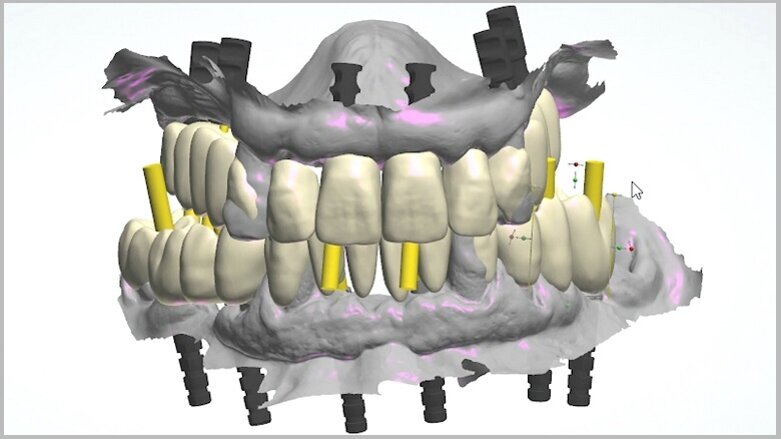

On receipt of the scan body file (File 2), the laboratory imported it into 3Shape’s Dental System and created a virtual model, matching the virtual SRA scan bodies from Straumann’s original library with the intra-oral SRA scan bodies (Figs. 13 & 14). A working file was created for designing the temporary prosthetic emergence profile for the SRA.

To perform the design of the temporary full-arch prosthesis and maintain (or modify) the vertical dimension of occlusion and occlusion, the patient’s pre-preparation study model scan file (File 1) was imported as a pre-preparation scan (blue) and merged with the implant file scan (File 2), using the preserved teeth present on both scans. The software allowed us to mark the same points on the preserved teeth on both files, the study model scan and the implant scan (both contained the preserved teeth). Thus, the laboratory was able to work on a single file containing both Files 1 and 2, merged by means of the preserved teeth. Designing the temporary prosthesis is an easy task using the image of the patient’s own teeth as a mock to be copied (Fig. 15). Any design modification can easily be done (Figs. 16 & 17).